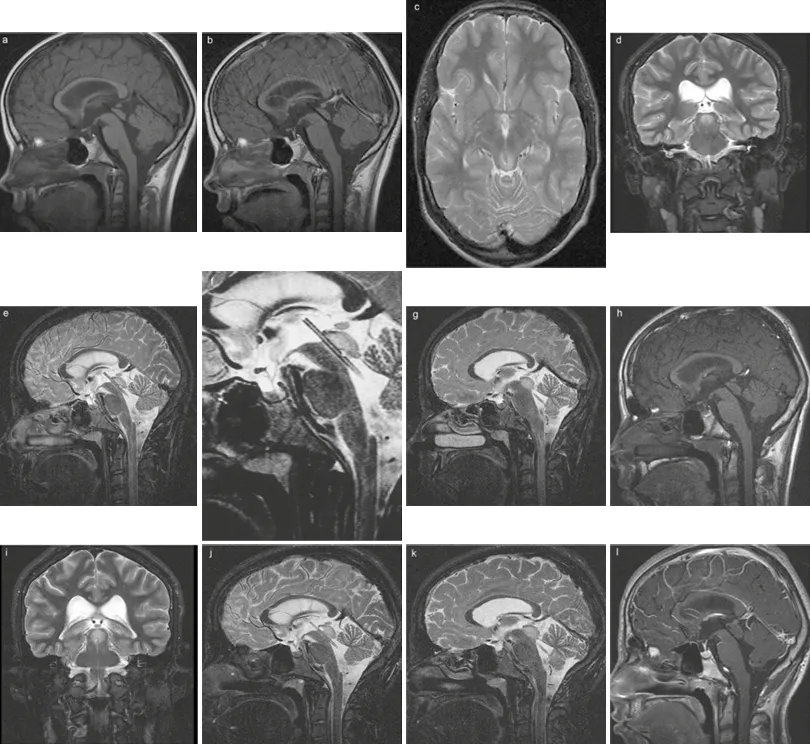

直至术后108个月(即9年)的长期随访,导水管支架功能依旧保持完好,患儿持续处于无症状状态,随访影像学结果令人满意(图4)。

图4:术后随访影像,分别显示在术后2年(a、b)、6年(c、d、e、f、g、h)以及9年(i、j、k、I)时的情况,均表明支架功能和位置完好。